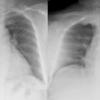

Lordotic combo

Ex 1

Date: 03/24/2004

Views: 4897